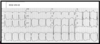

Interpret this EKG

Atrial Tachycardia with 2:1 AV block

Interpret this EKG

Atrial Tachycardia w/ 2:1 AV block